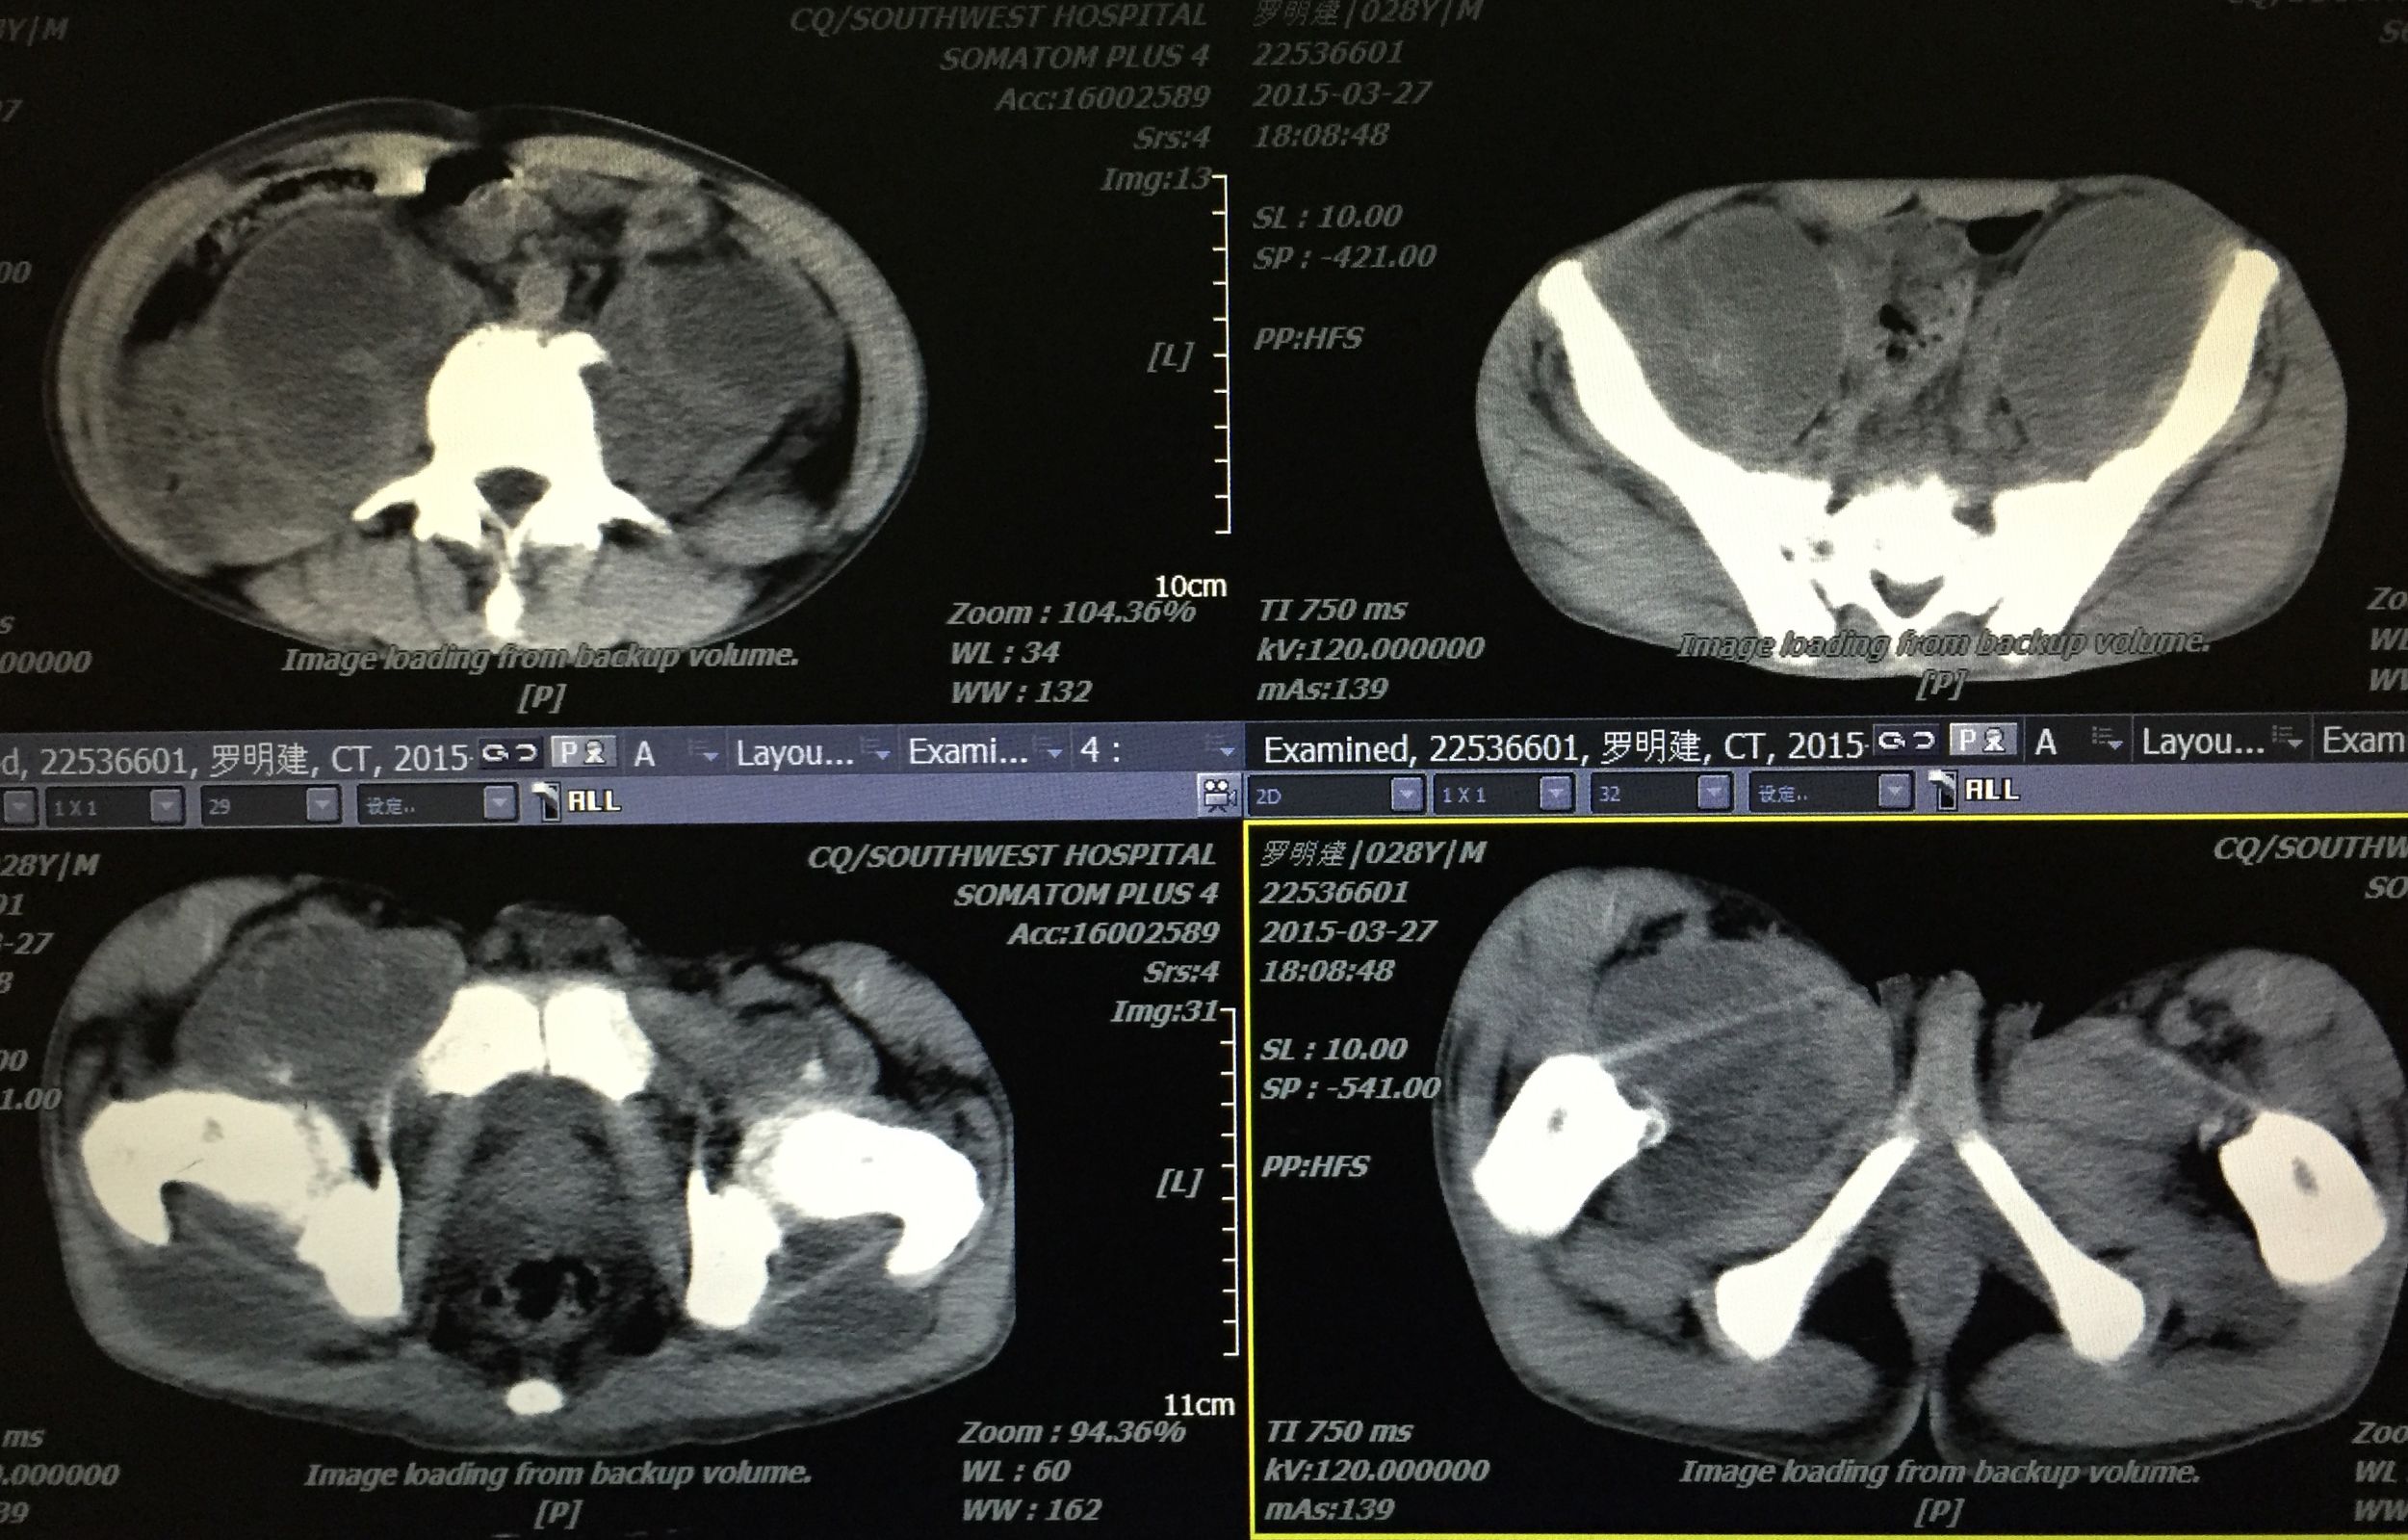

患者 29岁 盆腔及大腿根部多发结核脓肿(如图)

在门诊进行CT引导下穿刺引流术,植入五根引流管(如图白色条状物)

植入一月后,拔出两个引流管,剩余三根引流管仍有脓液溢出。

三月后患者全部拔出引流管。继续抗痨治疗